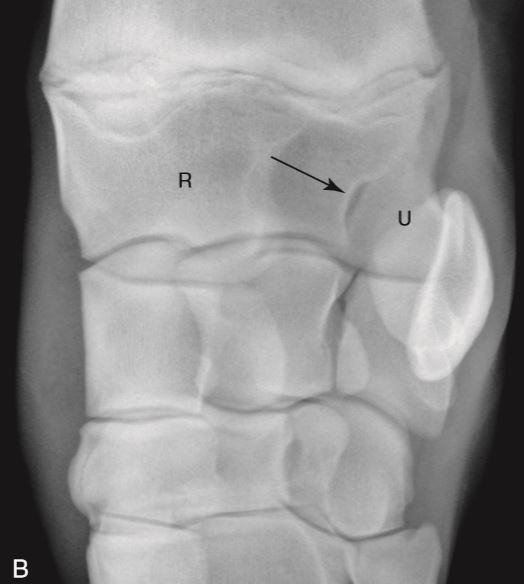

Q

Incomplete fusion of the epiphysis of radius and styloid process of the ulnar… normal variant